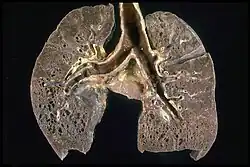

Respiratory tract

Localization to the lungs is by far the most common manifestation of sarcoidosis.[27] At least 90% of those affected experience lung involvement.[28] Overall, about 50% develop permanent pulmonary abnormalities, and 5 to 15% have progressive fibrosis of the lung parenchyma. Sarcoidosis of the lung is primarily an interstitial lung disease in which the inflammatory process involves the alveoli, small bronchi, and small blood vessels.[29] In acute and subacute cases, physical examination usually reveals dry crackles.[28] At least 5% of cases include pulmonary arterial hypertension.[28][30] The upper respiratory tract (including the larynx, pharynx, and sinuses) may be affected, which occurs in between 5 and 10% of cases.[31]

Histopathology

Sarcoidosis is characterized by the formation of non-necrotizing ("non-caseating") granulomas in various organs and tissues.[95] Giant cells, specifically Langhans giant cells, are often seen in sarcoidosis.[96] Schaumann bodies seen in sarcoidosis are calcium and protein inclusions inside of giant cells as part of a granuloma.[97] Asteroid bodies can be seen in sarcoidosis.[97] Hamazaki–Wesenberg bodies can be seen in lymph nodes and more rarely in lung biopsies with sarcoidosis and are inclusion bodies of lysosomes with protein, glycoprotein and iron.[98]